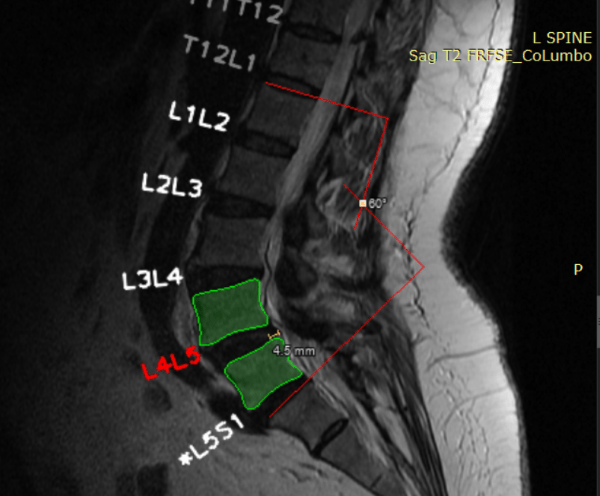

Madrid, 11 de abril de 2023: Unilabs, proveedor líder de servicios de diagnóstico, se ha asociado con SmartSoft Healthcare para implementar en España su solución de IA, CoLumbo, con el fin de mejorar la lectura y los informes de resonancia magnética de columna lumbar.

"Estamos encantados de colaborar con SmartSoft Healthcare para poner esta innovadora solución a disposición de nuestros pacientes en España. CoLumbo actúa como un par de ojos digitales adicionales y ayuda a los radiólogos a detectar patologías significativas en los exámenes de RM de columna lumbar. Creemos que CoLumbo mejorará la calidad y eficiencia de nuestros exámenes de RM de columna lumbar y beneficiará en última instancia a nuestros pacientes y radiólogos", señaló el Dr. Christian Rebhan, presidente de las Unidades de Negocio Científicas y director médico de Unilabs. "Estamos muy contentos de ser el primer país en probar esta solución. Nuestro equipo técnico ha integrado perfectamente la herramienta en el flujo de trabajo de nuestros radiólogos, garantizando que se pueda utilizar de forma cómoda y eficiente", añadió el director general de Unilabs España, Rainiero Holgado.

CoLumbo reduce el tiempo de lectura e informe de los radiólogos hasta en un 25 %, lo que aumenta el número de pacientes examinados al tiempo que mejora la precisión del diagnóstico. Ensayos clínicos han concluido que CoLumbo puede reducir los errores por omisión hasta en un 15 %.

CoLumbo ha recibido el Sello de Excelencia de la Comisión Europea, y el proyecto ha obtenido la marca CE y cumple la normativa sobre sistemas de calidad de la FDA, además de contar con la autorización 510(K) de la FDA, por lo que está autorizado para su uso clínico tanto en Europa como en Estados Unidos. También está pendiente de patente en la USPTO US 63/239,985.